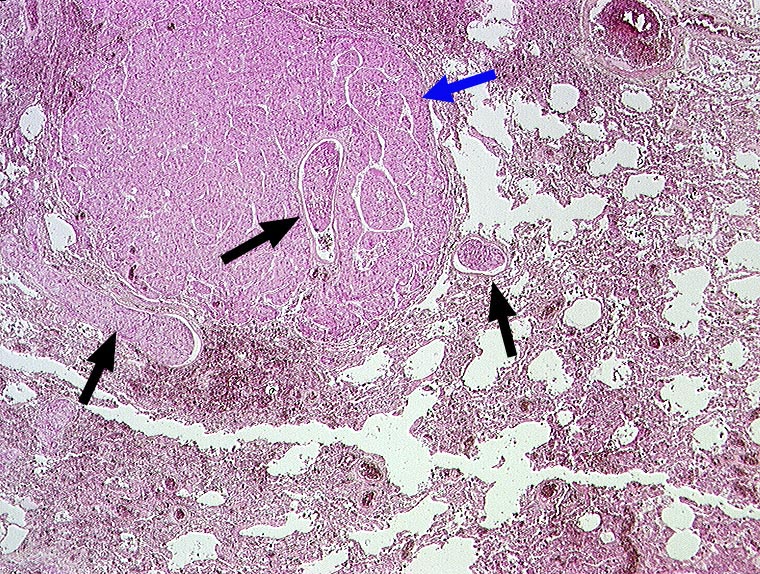

AP/ Hepatozelluläres Karzinom: Lungenmetastasen

Hepatozelluläres Karzinom: Lungenmetastasen

maligner Tumor

Lunge, Mediastinum mit Thymus

Lunge